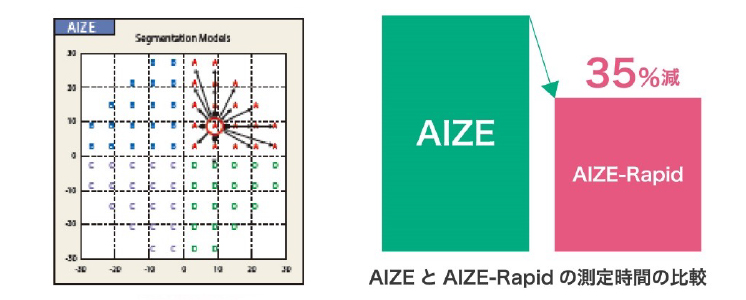

オリジナルプログラム「AIZE」

imoに搭載されているオリジナルプログラム「AIZE(Ambient Interactive ZEST:アイズ)」は、隣接する周囲の検査点と相互作用しながら、ZEST*の基本的なアルゴリズムで網膜感度閾値を決定します。 これにより、高精度の視野測定と測定時間の短縮を実現しました。

オリジナルプログラム「AIZE-Rapid」

従来のオリジナル検査アルゴリズムAIZE(アイズ)よりも検査時間の短縮を実現させたAIZ-Rapid®AIZEの基本ストラテジーは変えずに、検査点での被験者の反応に対して隣接する他の検査点により強く反映させ、さらに偽陰性・偽陽性・固定監視を検査プロセスから推定させることにより、閾値の決定に必要な試行回数を減らすことになり時間短縮を実現しました。